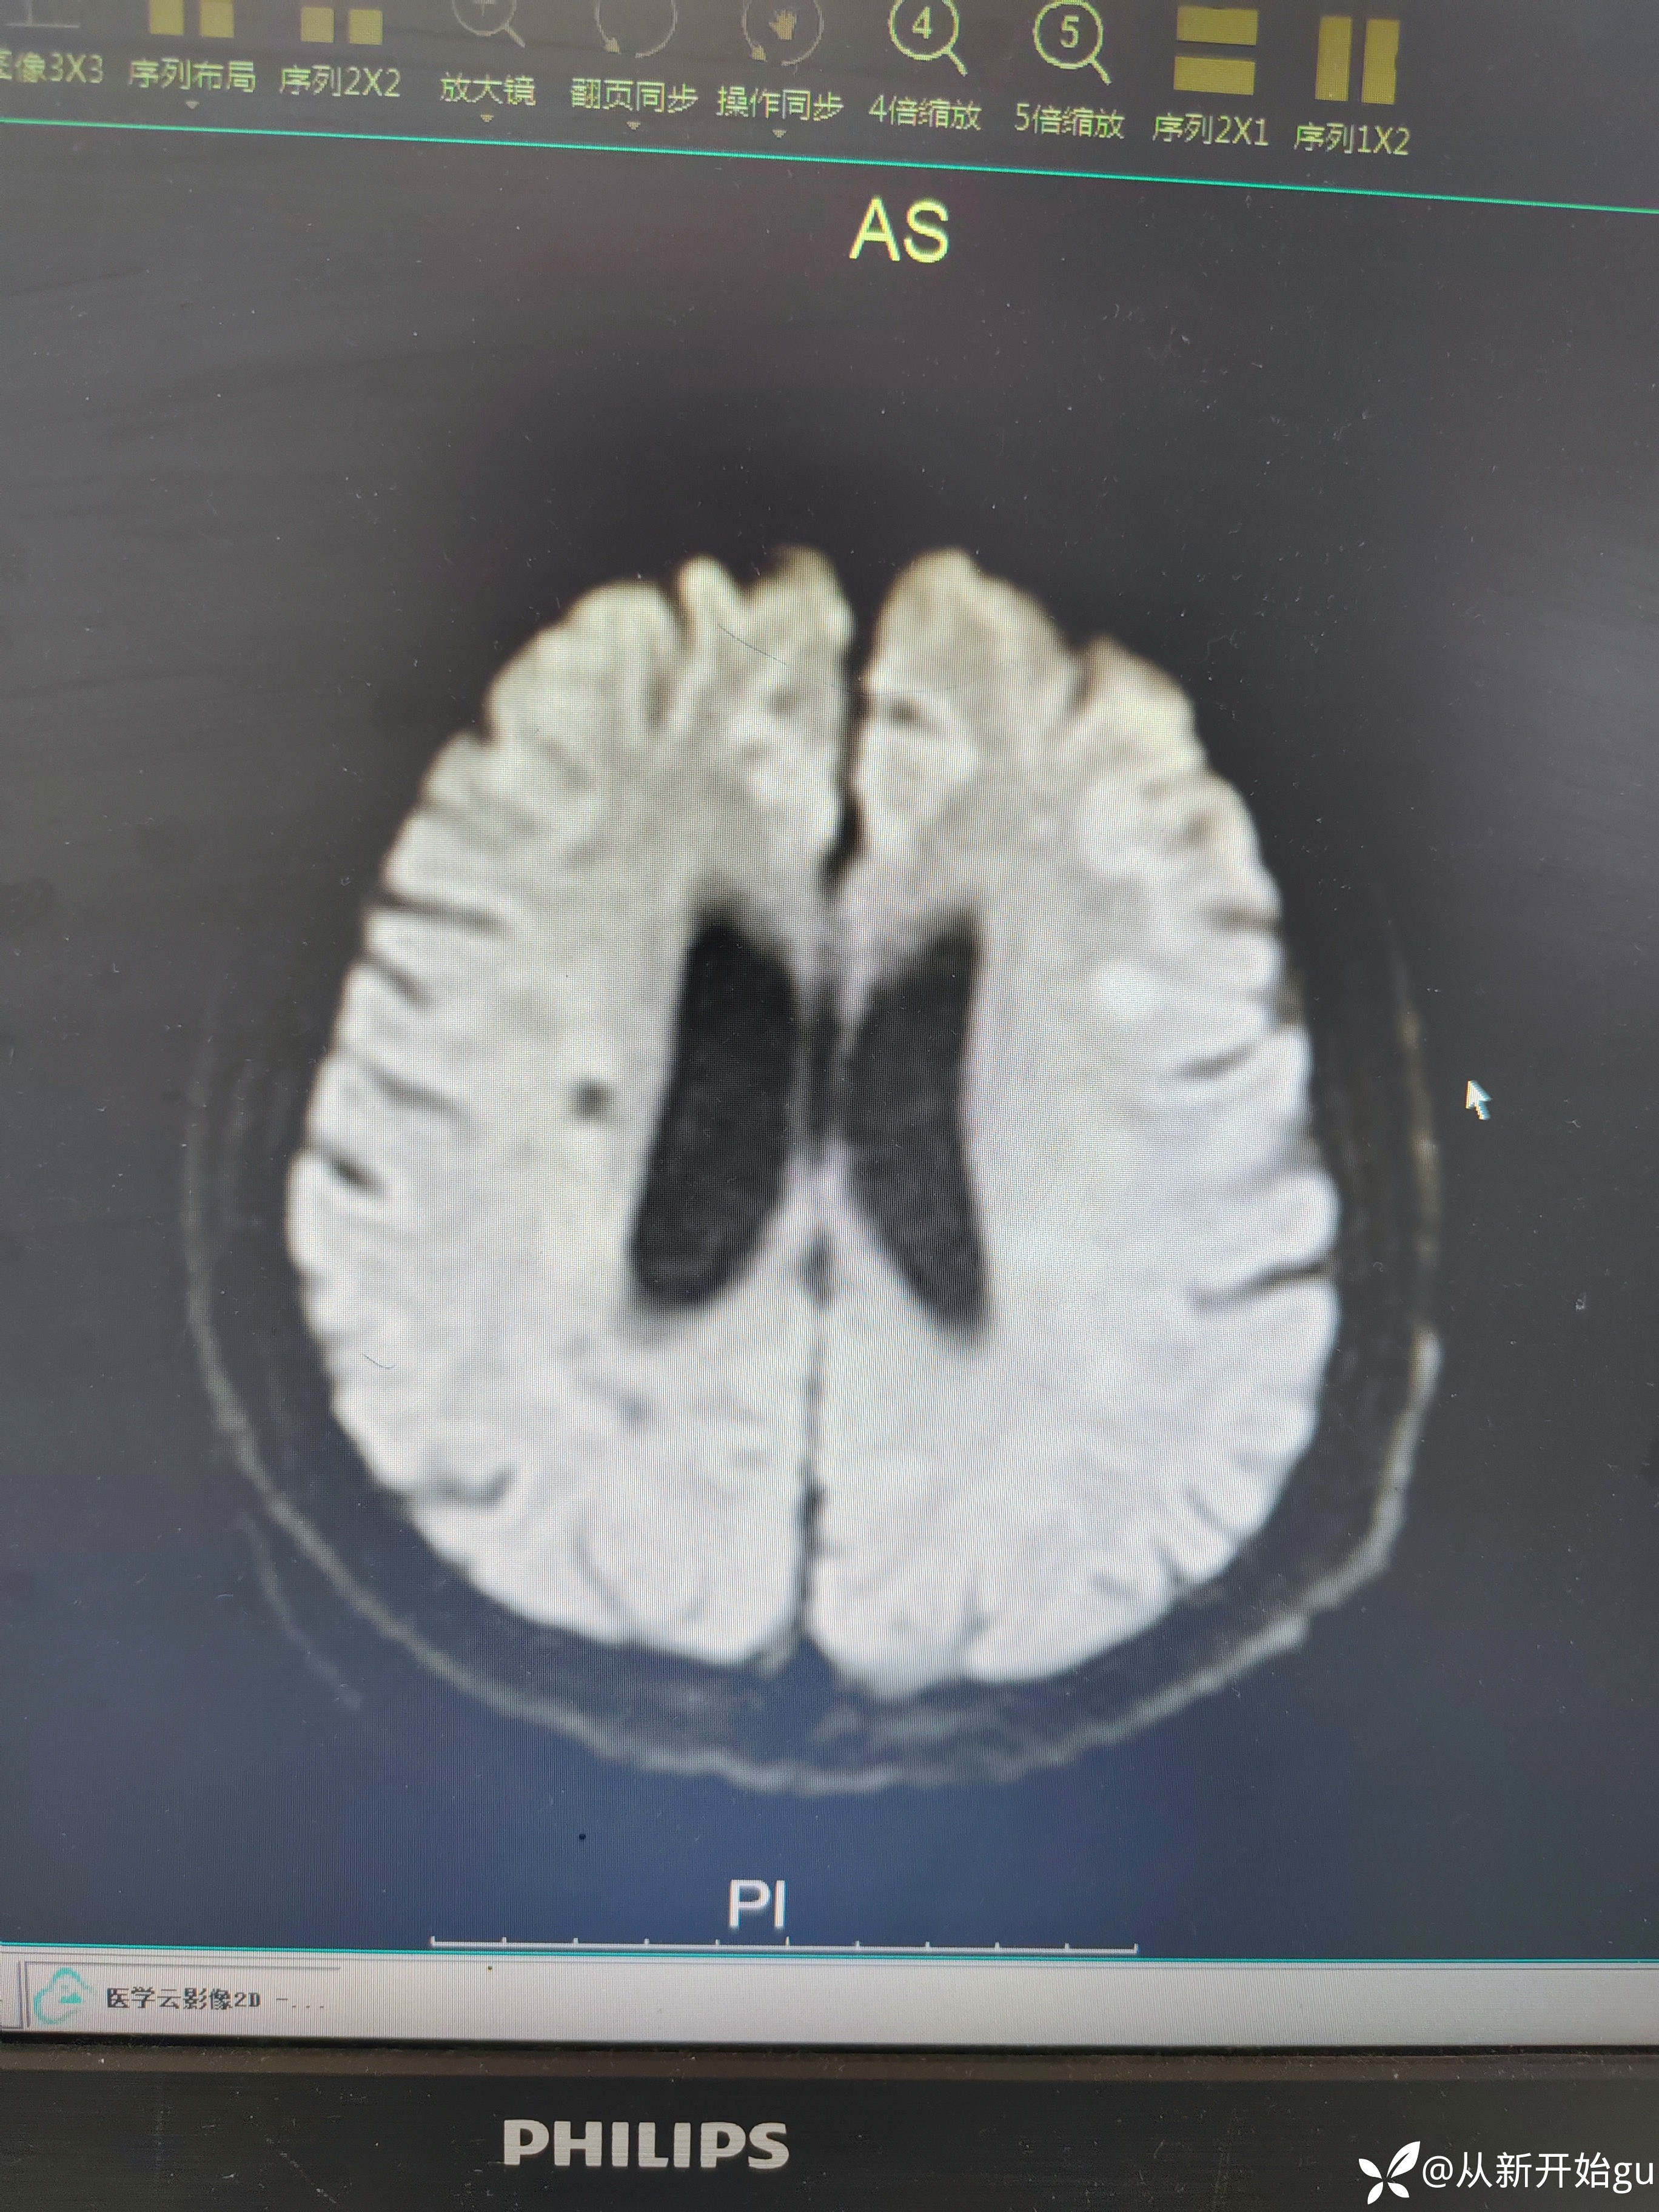

患者男性53岁,主因被发现左下肢活动障碍2.5小时来院,(患者下夜班,于上午9点休息,下午3点醒后出现症状)。既往脑梗死病史9个月,遗留言语不利及口角歪斜的症状。查体:右侧鼻唇沟稍浅,神舌右偏,左侧下肢肌力4级,左侧指鼻试验欠稳准,左侧巴氏征阳性。外院完善颅脑CT无出血改变。来院后完善核磁检查如图所示。